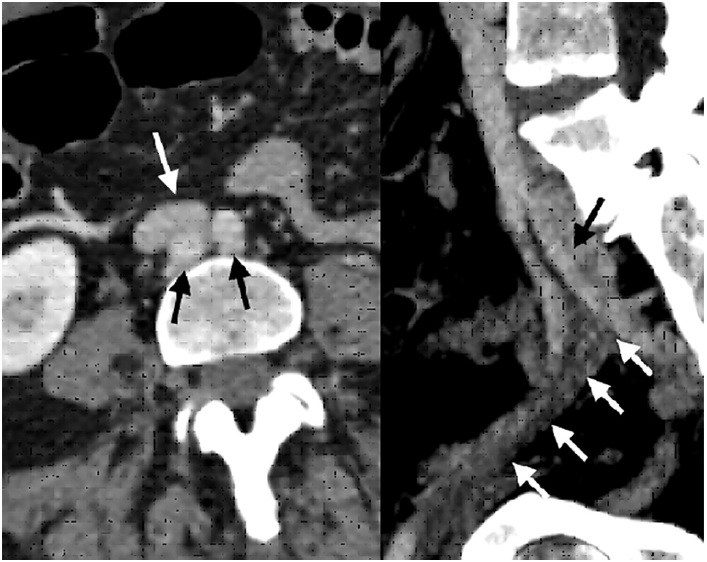

Mujer de 55 años, previamente sana, que consulta por cuadro de edema marcado de todo el miembro inferior izquierdo, con dolor incapacitante, coloración azulada-violácea del miembro y parestesias en el pie, que comenzó una semana previa a la consulta y que fue empeorando al punto de inhabilitar la marcha. Al examen físico era notable el edema desde el pie hasta la raíz del muslo, tenso, así como la ausencia de pulsos distales con solo señales monofásicas por Doppler sin alteración de la función motora. El eco Doppler reveló una TVP que involucraba las venas femoral común, femoral proximal y femoral profunda, y también la vena safena magna, por lo que se decidió iniciar de inmediato anticoagulación con heparina de bajo peso molecular. La angiotomografía mostró una extensa TVP desde la vena ilíaca externa izquierda proximal hasta la vena poplítea, al igual que una bifurcación aórtica retrocava, con compresión a nivel de la confluencia de las venas ilíacas externa e interna, entre el sacro y la arteria hipogástrica izquierda (Figura 1).

Imagen de estudio dividida en 2

Fig. 1 Izquierda. Corte axial de angiotomografía que evidencia bifurcación aórtica (flechas negras), por detrás de la confluencia iliocava (flecha blanca). Derecha. Corte sagital que objetiva compresión por la arteria hipogástrica izquierda (flecha negra) que causa trombosis de la vena ilíaca externa (flechas blancas).